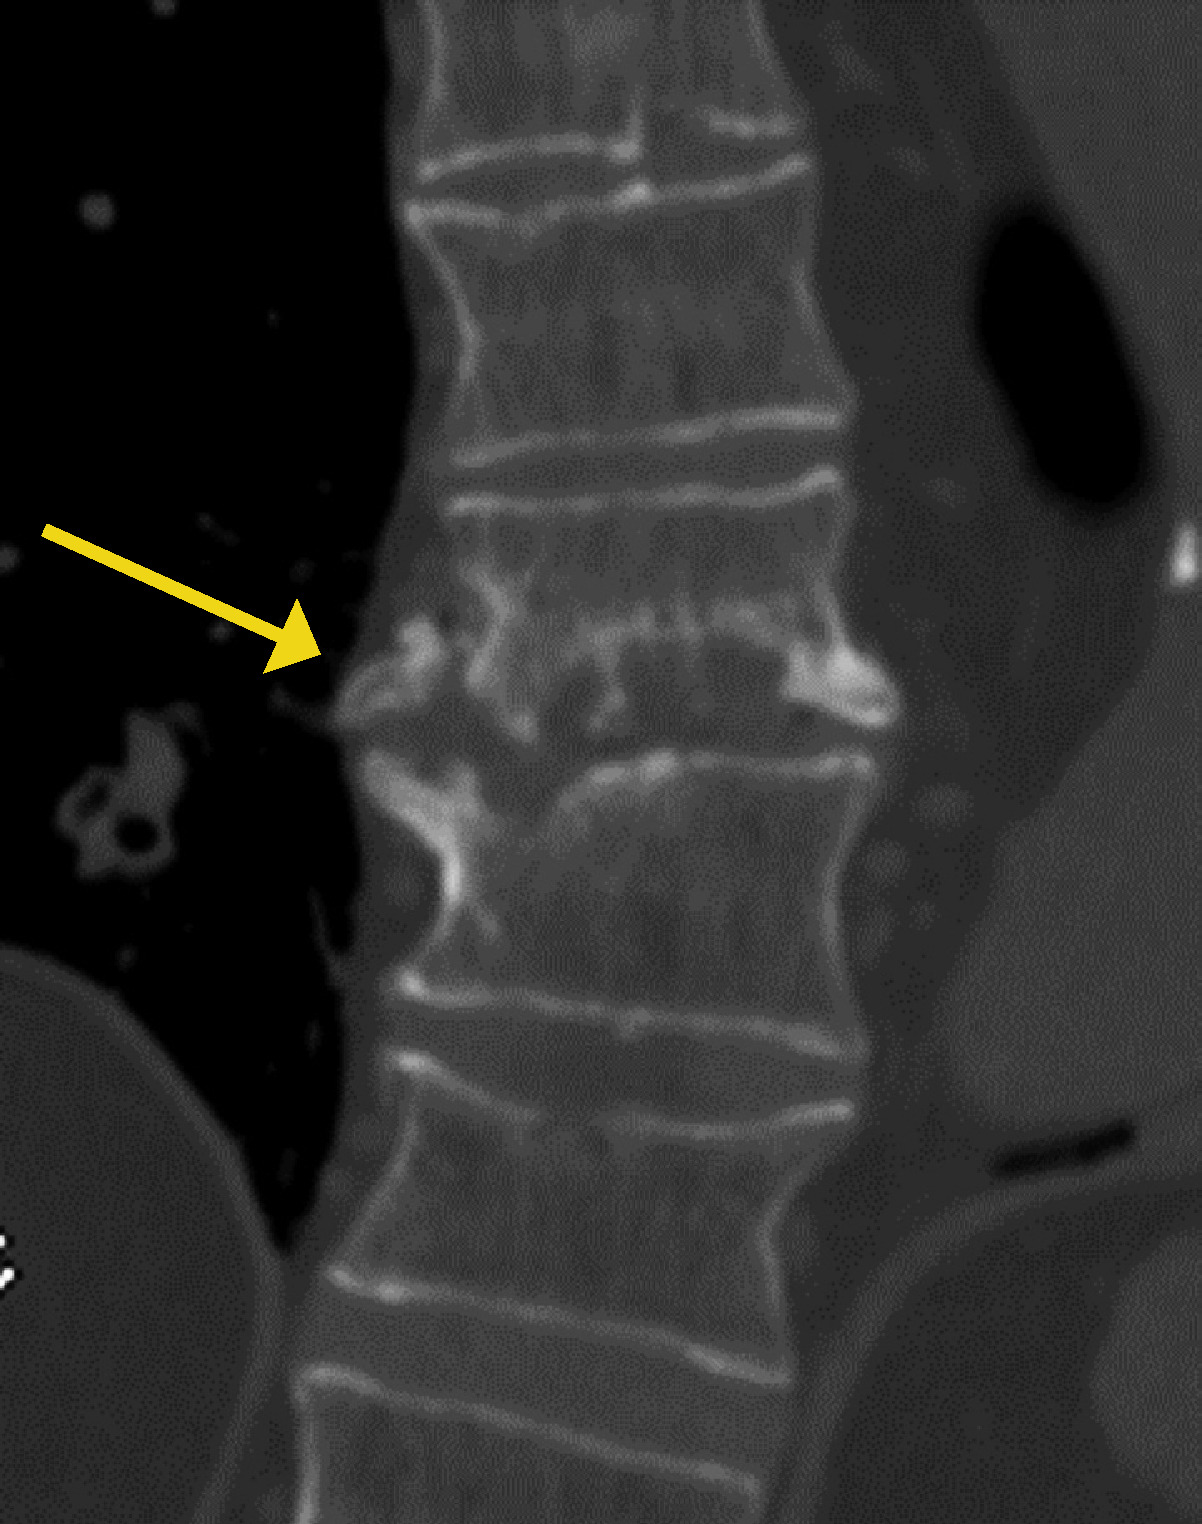

- El síndrome de Bertolotti es una causa frecuente de dolor lumbar en pacientes jóvenes, y se caracteriza por el agrandamiento anómalo de las apófisis transversas de la vértebra lumbar más caudal, que puede articular o fusionarse con el sacro o ilion.